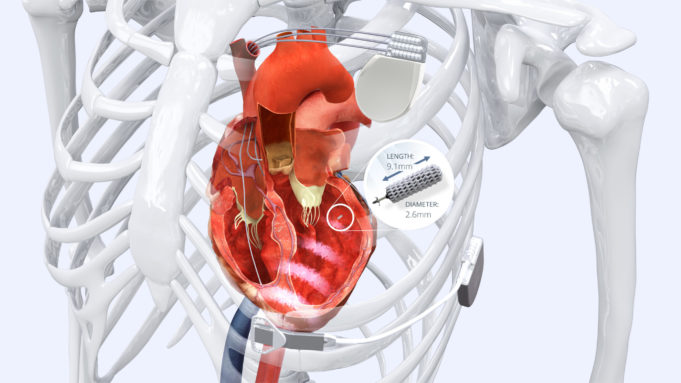

Medtronic has received CE mark for Micra AV Transcatheter Pacing System (TPS), the world’s smallest pacemaker with atrioventricular (AV) synchrony.

Micra AV is indicated for the treatment of patients with AV block, a condition in which the electrical signals between...

Medtronic has announced that it has received US Food and Drug Administration (FDA) approval of Micra AV, the world’s smallest pacemaker with atrioventricular (AV) synchrony.

Micra AV is indicated for the treatment of patients with AV block, a condition in...